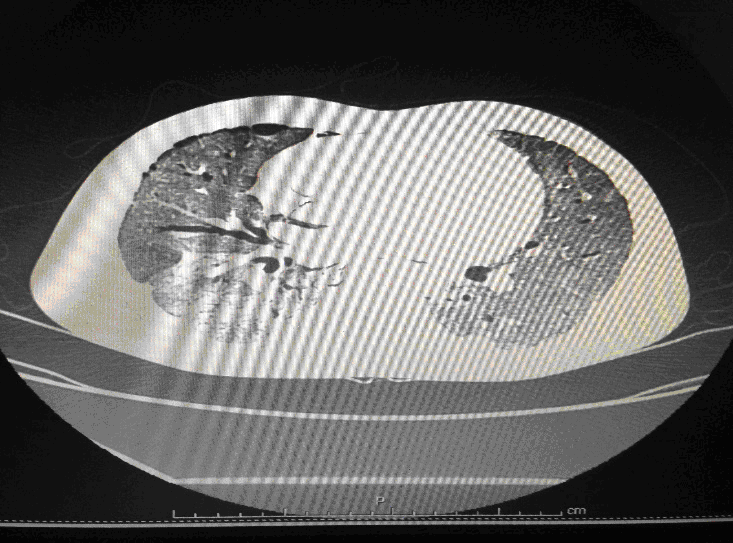

Following admission in the Medical ICU, Bronchoscopy was done and started on IV steroids and higher End Antibiotics. His bronchial wash grew ESBL Klebsiella and Pseudomonas. His other organ functions were not deranged. Repeat CT Thorax was taken which showed ground glass opacities, septal thickening, traction bronchiectasis, pleural thickening which was all S/o Drug induced Toxicity-Bleomycin.

Typical chest radiographic findings are bilateral, bibasilar infiltrates, sometimes followed by diffuse interstitial and alveolar infiltrates. Fine nodular densities and subpleural opacification with volume loss and blunting of costophrenic angles may also be present. These early findings may evolve to progressive consolidation and honeycombing [23] Pneumothorax and pneumomediastinum are rare complications of bleomycin-induced pulmonary fibrosis .

High-resolution computed tomography (HRCT) of the chest is more sensitive than chest radiography in identifying lung abnormalities in bleomycin-exposed patients. HRCT patterns usually reflect the underlying histopathology . Diffuse alveolar damage is associated with airspace consolidation and ground-glass opacities. Findings suggestive of end-stage fibrosis include extensive reticular markings, traction bronchiectasis, and honeycombing. Organizing pneumonia manifests as ground-glass opacities in a bilateral but asymmetric pattern or by airspace consolidation with a subpleural or peribronchial distribution. Organizing pneumonia may occasionally present as one or more nodular densities that may mimic tumor metastases.